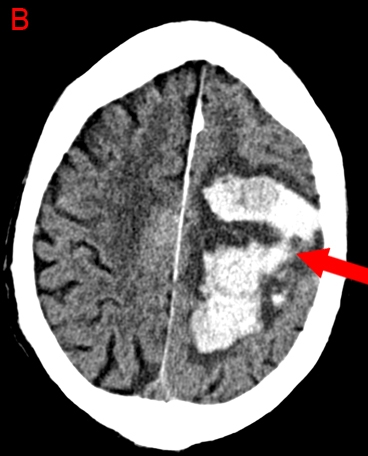

Cerebral Amyloid Angiopathy

Cerebral amyloid angiopathy is the second most common cause of intracerebral hemorrhage after hypertension and is typically lobar in location. It most often occurs in patients age >75 and is due to abnormal beta-pleated amyloid protein deposition in cerebral blood vessels, leading to arteriopathy and vessel fragility.

Brain bleeds